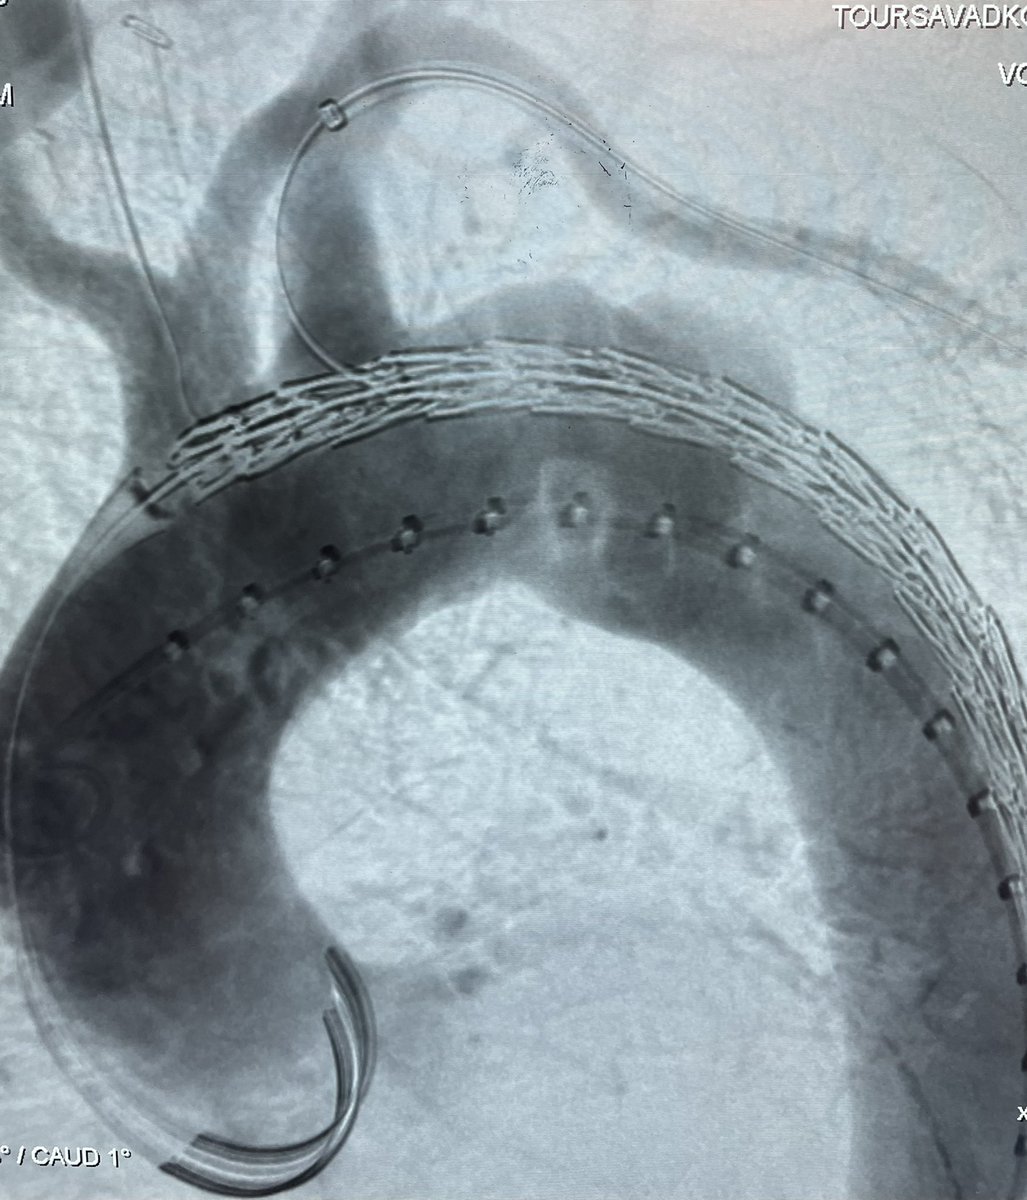

Great outcome using GORE TBE in an emergency case with replaced right SCA and zone 3 contained rupture PAU. Thanks to collaboration of Vascular and Cardiac surgery team. @MarylandSurg @UMMC The first commercial use of TBE in Maryland

@SToutsavadkohi @dr_ghoreishi @BtaylorMD2